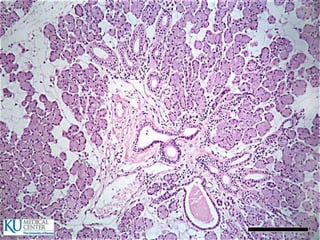

Especializaciones superficiales de lamucosa  Pliegues circulares (válvulas de Kerckring)  Vellosidades y criptas  Microvellosidades  Tipos de glándulas:  Intestinales  Submucosas (Brunner)  Situadas fuera del tubo digestivo

• 63.

Intestino delgado  Epitelio: Células cilíndricas  Células de Paneth  Células caliciformes  Células enteroendócrinas

• 64.